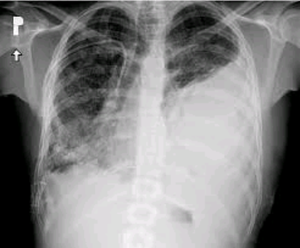

Your diagnose ?

Collapsed lung, or ?

Pneumothoracique

Pleural effusion